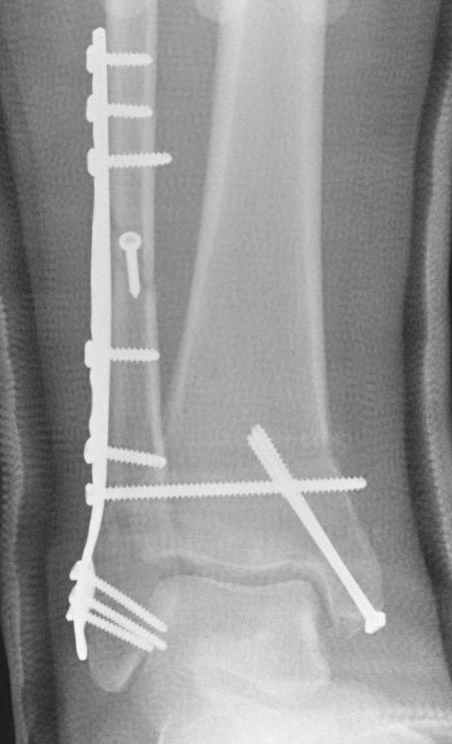

Если до сих ничего не сделано, с артродезом сустава в данный момент я бы повременил, на выставленных январских снимках хорошо сохранившийся сустав, а в "мортиз" (трехчетвертной) и на боковых снимках не менее 5 мм укорочение малоберцовой кости. Косые переломы лучше фиксировать пластинами, как то мы разбирали случай, где было отмечено, что это закон "таранная кость всегда следует за малоберцовой".

В данном случаи я бы уговорил больного на реконструкцию, для этого после удаления шурупов, спереди очистить от рубцов синдесмоз, несросшуюся наружную лодыжку - остеотомия по линии перелома и компрессирующий (lagging technique) кортикальный шуруп 3.5 мм по поперечнику остеотомии. Следующий этап - восстановление длины малоберцовой за счет удлинения, сделать поперечную остеотомию где-то на уровне сантиметр выше вашего синдесмозного шурупа, наложить длинную пластинку, прикрепить пластину за дистальный конец двумя или тремя шурупами; сохраняя контакт пластины с костью, имеющимся

compression&tension device AO system (при отсутствии любой lamina spreader подойдет, создать дистанцию между пластиной и шурупом, проведенным проксимальнее пластины) толкая проксимальный отдел пластины, низвести пластину, мортиз рентгенограмма подскажет на сколько. Если заранее сделать предоперационный план (ренгенограмма другой стороны), тогда точно можно определить, на сколько вам необходимо сделать поперечную остеотомию малоберцовой кости, для закрытия создавшегося дефекта.

Убедившись, что желаемая длина восстановлена, окончательная фиксация пластины, при этом через пластину пару 3.5 мм шурупов на синдесмоз, предпочтительно в четыре кортекса и оставить на 3 мм длиннее, если под нагрузкой синдесмотический шуруп сломается, сломанный конец легче удалить с медиальной стороны.

Медиальная сторона не в нагрузочной зоне, и там большая дыра - если есть 2.7 мм шурупы, или пару спиц в ваших условиях или методика Лазарева. Необходимо уделить внимание к мягким тканям, обнажается кость с латеральной стороны и у места где проводится остеотомия.